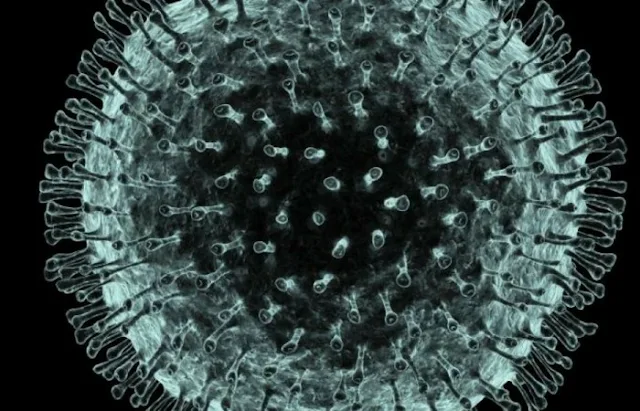

দেশে গত ২৪ ঘণ্টায় নতুন করে করোনাভাইরাস শনাক্ত হয়েছে আরও ২ হাজার ৬৫৪ জনের দেহে। এ নিয়ে দেশে মোট শনাক্ত হলেন ২ লাখ ৪৬ হাজার ৬৭৬ জন। এছাড়া আক্রান্তদের মধ্যে আরও ৩৩ জনের মৃত্যু হয়েছে। এ নিয়ে মোট মৃতের সংখ্যা দাঁড়াল ৩ হাজার ২৬৭ জন।

উল্লেখ্য, গত ৮ মার্চ দেশে প্রথম করোনাভাইরাসে আক্রান্ত রোগী শনাক্ত হয় বলে জানায় সরকারের রোগতত্ত্ব, রোগনিয়ন্ত্রণ ও গবেষণা প্রতিষ্ঠান (আইইডিসিআর)। আর ১৮ মার্চ প্রথম একজনের মৃত্যুর সংবাদ জানানো হয়।